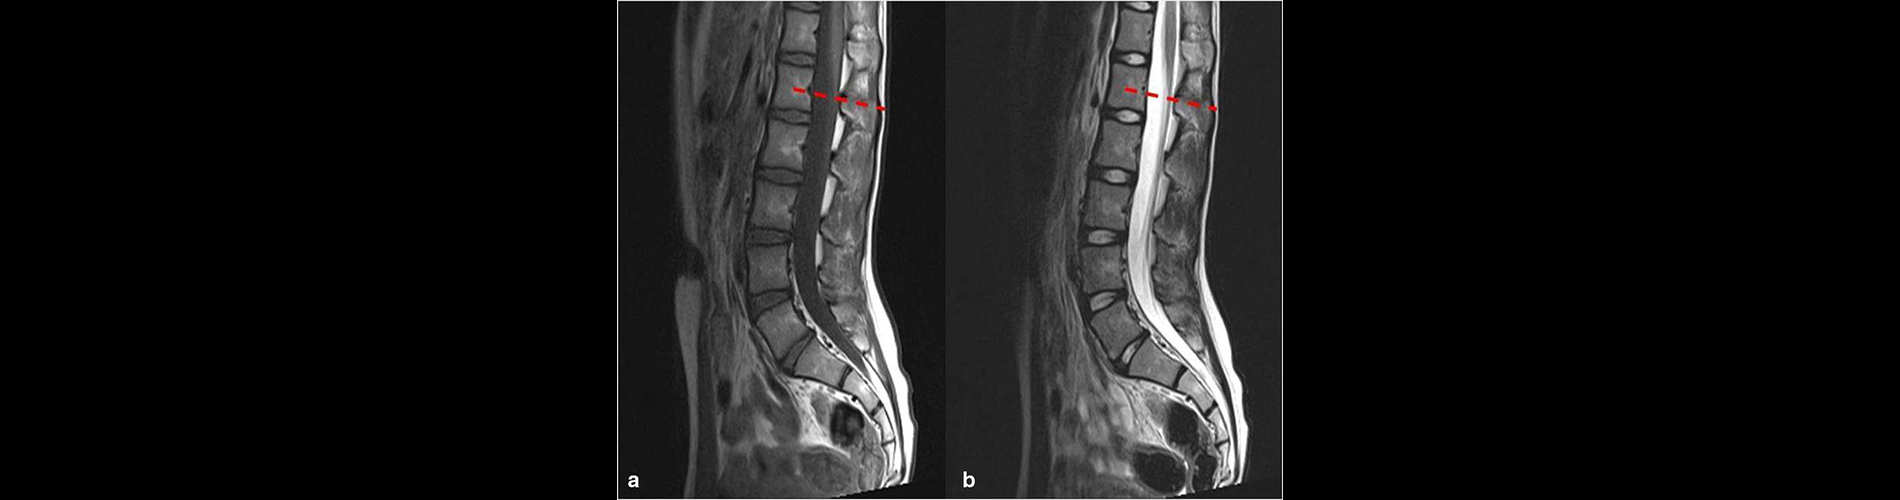

Lomber MR , bel bölgesindeki (lomber omurga) omurlar, omurilik, sinir kökleri, diskler ve çevre yumuşak dokuları detaylı bir şekilde görüntülemek için kullanılan bir yöntemdir. Radyasyon içermemesi ve yumuşak dokuları çok net görüntüleyebilmesi nedeniyle bel hastalıklarının teşhisinde sıkça tercih edilir.

• Odak Alanı: Bel bölgesindeki omurlar (L1-L5), sakral omur, omurilik, sinir kökleri, intervertebral diskler, bağlar ve yumuşak dokular.

1. Detaylı Görüntüleme: o Omurga, diskler, sinir kökleri ve çevre dokular yüksek çözünürlükte görüntülenir.

3. Doğru Tanı: o Bel fıtığı, sinir kökü basısı veya spinal stenoz gibi sorunların doğru teşhisinde etkilidir.

5. Ameliyat Planlaması: o Cerrahi müdahaleler öncesinde detaylı anatomik bilgi sağlar.